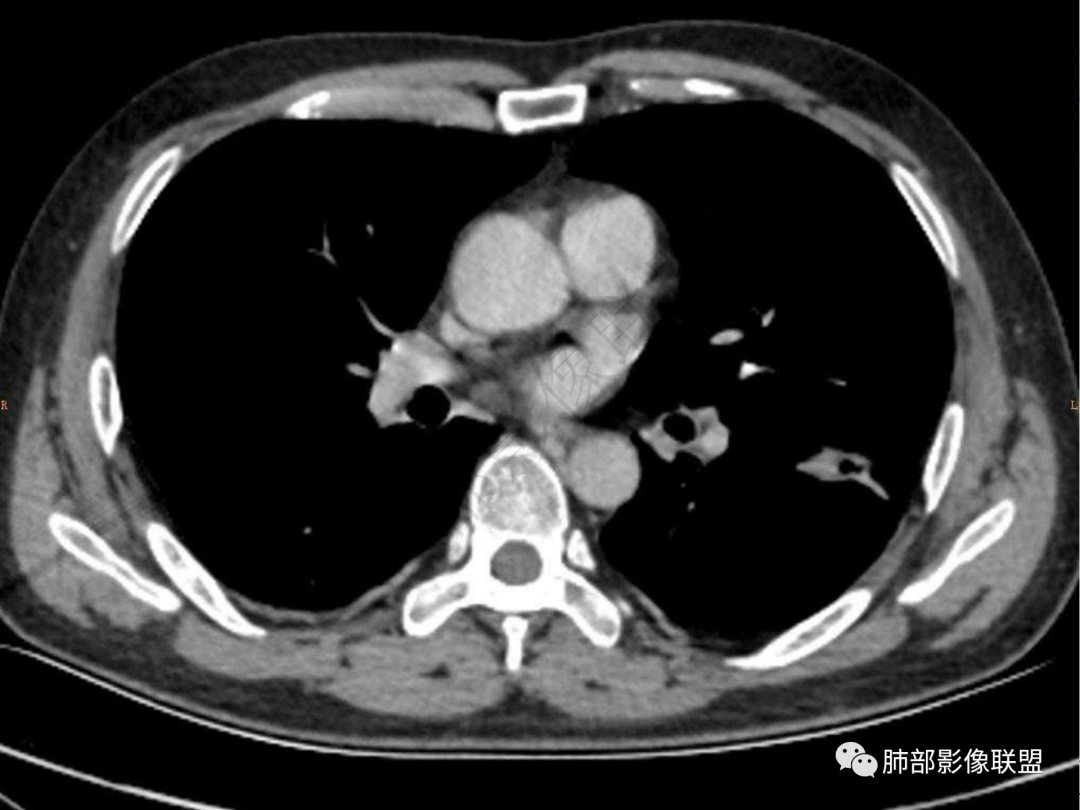

1.中年男性,咳嗽咳痰20余天,间断咯血2周

2.左肺下叶团片影,跨背段及内前基底段,实性部分类椭圆形,密度不甚均匀,可见毛刺及棘状突起,未见典型分叶及胸膜凹陷。病灶上下缘可见相应肺段支气管旁进侧出,管壁轻度增厚,未见狭窄阻塞。

3.周边较大范围磨玻璃影,边界相当模糊,小叶增厚明显。注意叶裂另一侧、左肺舌段亦可见磨玻璃影及增厚的小叶间隔。未见明确卫星病灶。

4.实性部分不均匀环形强化并显示一小范围低密度坏死区或空洞。较之肺窗,整体纵隔窗范围较小,提示病灶并不十分密实。抑或为不同时段图像。

5.双肺门及纵隔未见增大淋巴结。未见胸腔积液。